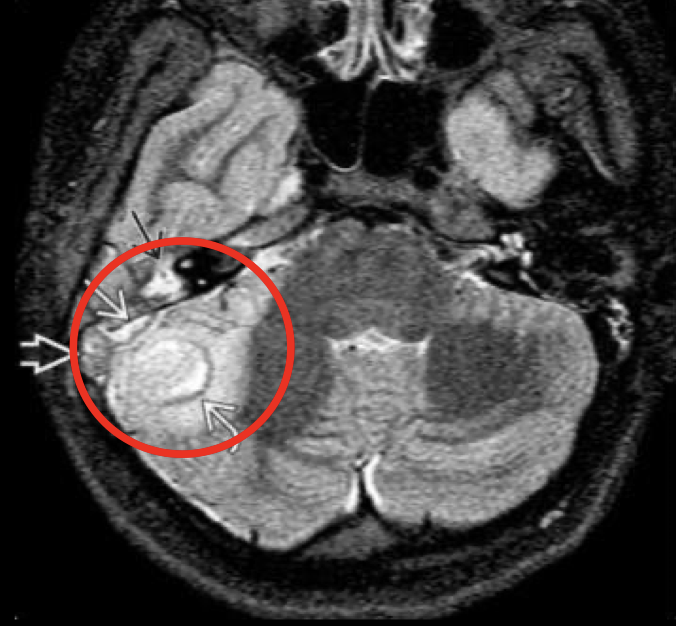

Q

RM mastoiditis